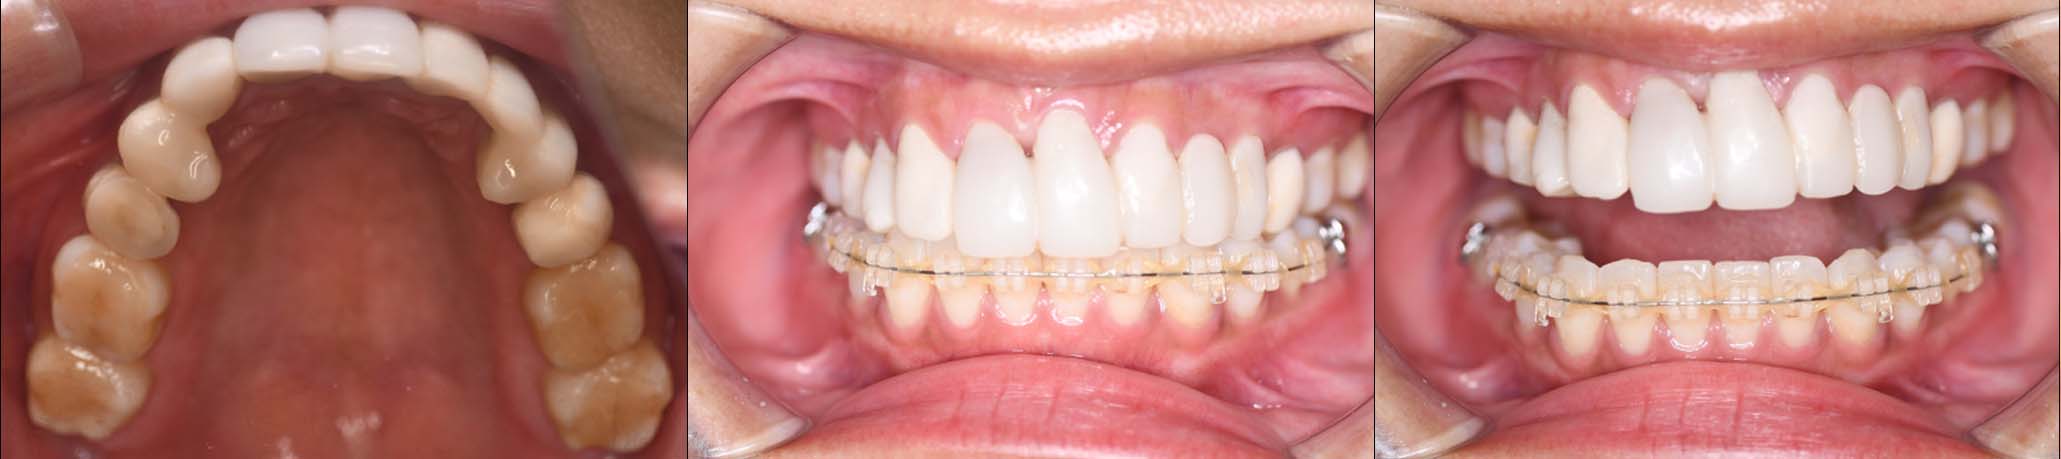

2024年 10月 下顎MTM開始

2024年 10月10日

10月21日

11月7日

11月28日

12月16日

12月23日

1月9日

1月30日

2月20日

3月13日

4月24日

9月25日